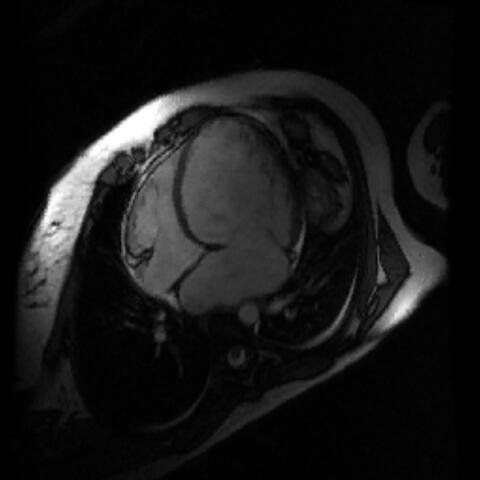

Ein gesundes Herz… Abb.: J. Fielitz/​MDC